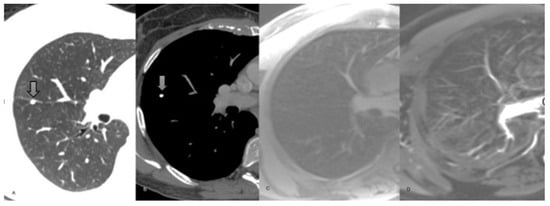

3. Results

3.2. MR Findings

4. Discussion